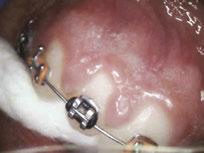

Over 10 years ago, we began Orthotropic® treatment for a 5 year, 3-month-old boy with a diagnosis of Pierre-Robin Sequence, Obstructive Sleep Apnea (OSA), and Failure to Thrive (Figure 1). With lack of forward development of the face com-

monly seen in Pierre-Robin patients, his airway was compromised, resulting in OSA. The Failure to Thrive diagnosis likely resulted from insufficient growth hormone being released during the deeper stages of sleep. This treatment began before any permanent teeth erupted. Our goal was to eliminate OSA.

Orthotropics® uses removable appliances to laterally expand the upper arch while simultaneously advancing the upper anterior teeth to their proper place in the face. Then the mandible is developed forward. Orthotropics® is my preferred treatment in cases like this because it negates the head gear-effect producing better facial balance5 and also can result in substantial airway improvements (Figure 2).6

Figure 1: Pretreatment gallery Figure 3: Today, he’s a tennis player Figure 2: Pre- and posttreatment airways